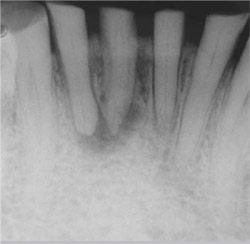

A 62-year-old man needing treatment of teeth Nos. 23 through 26 was referred to our clinic for evaluation due to periapical radiolucencies in the above mentioned teeth (Figure 1). He reported a period of cold and hot sensitivity 8 months prior but had not had any temperature tenderness for several months. The pulpal and apical diagnosis was necrosis in addition to chronic apical periodontitis.

| Figure 1 Preoperative radiograph of teeth Nos. 23 through 26. Note the loss of coronal tooth structure. | Figure 2 Preoperative radiograph of tooth No. 8 showing the previous metal post and failed root canal treatment. | ||||||||